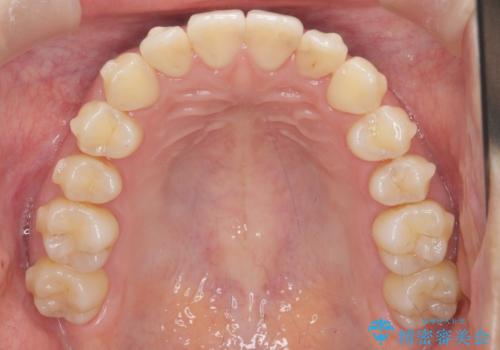

ワイヤー部分矯正治療を併用したマウスピース矯正治療

- 前歯のねじれ、深い噛み合わせ(ディープバイト)の改善を求めて来院されました。

マウスピースでは改善の難しい、歯のねじれ・ディープバイトを部分ワイヤー矯正で改善したのち、マウスピース矯正で全体の歯並びを整えていきます。

部分ワイヤー矯正を行ったことで前歯をしっかりと綺麗な歯並びへと導くことができました。